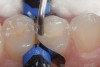

3. A composite placing instrument (Flexi-Thin Mini 4, Hu-Friedy, www.hu-friedy.com) is used to shape occlusal morphology on this bulk-filled composite restoration (Tetric EvoCeram Bulk Fill, Ivoclar Vivadent) prior to light curing.

Figure 3